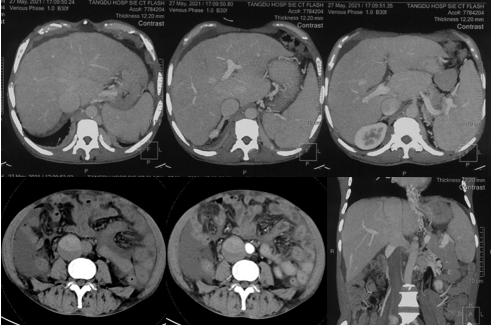

6月20日,患者及家屬懷揣著忐忑的心情來到西安國際醫(yī)學(xué)中心醫(yī)院找到韓國宏教授,韓教授詢問病情后閱患者外院CT片,明確診斷布加綜合征,同時(shí)發(fā)現(xiàn)了一個(gè)新的問題,在詢問病史時(shí)了解到患者近一周雙下肢乏力伴腫脹明顯加重,遂立即安排了急診CT,證實(shí)下腔靜脈內(nèi)急性血栓形成!

6月22日,在韓國宏教授的帶領(lǐng)下,患者于消化介入診療中心行下腔靜脈開通術(shù)。術(shù)中可見:下腔靜脈全段擴(kuò)張,膜性閉塞,腎靜脈平面以下可見血栓形成并伴有粗大的側(cè)枝靜脈,遂對狹窄段球囊擴(kuò)張并植入支架,術(shù)后下腔靜脈血流通暢,側(cè)枝消失。術(shù)后第2天,患者腹壁靜脈曲張幾乎消失不見,走路也輕快了許多。明明只是薄薄的一層膜,為什么開通起來這么難?韓教授指出,盡管布加綜合征介入開通技術(shù)已使創(chuàng)傷降到了最低,但受到患者個(gè)體差異及醫(yī)療水平參差不齊的限制,仍有可能出現(xiàn)嚴(yán)重的并發(fā)癥,主要包括:心包積血、縱隔血腫、心包填塞甚至下腔靜脈撕裂引起的大出血等。而其發(fā)生率與術(shù)者的操作熟練程度及經(jīng)驗(yàn)有很大的關(guān)系。